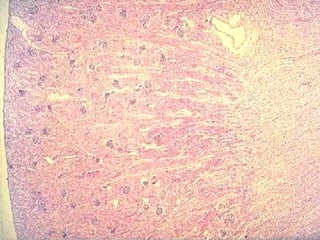

Aparato yuxtaglomerular El aparato yuxtaglomerular regula la presión arte-rial mediante la activación del  sistema renina-angiotensina-aldosterona. Comprende la  mácula densa , las  células yuxtaglomerulares  y las  células mesangiales extraglomerulares .

Mácula densa La  mácula densa  regula la secreción de renina de acuerdo con la composición del líquido tubular en el túbulo distal, por lo que una  hiponatremia  ( disminución de la concentración de sodio en sangre ) o  hiperpotasemia  ( aumento de la concentración de potasio en sangre ) implica un aumento en la secreción de renina. El incremento de líquido en el túbulo distal, produce la expansión de este lo cual inhibe la secreción de renina.

Células yuxtaglomerulares   En esta misma región las células musculares lisas de la arteriola aferente (y, a veces, de la arteriola eferente) contigua están modificadas.  Contienen gránulos de secreción y sus núcleos son redondeados. Estas  células yuxtaglomerulares  (o  células JG ) están en íntimo contacto con las células de la mácula densa y sólo las separa una lámina basal incompleta.

Sistema  renina-angiotensina-aldosterona  (SRAA) En algunas situaciones fisiológicas (ingesta reducida de sodio) o patológicas (disminución del volumen sanguíneo circulante por hemorragia o baja perfusión renal por compresión de las arterias renales) las células yuxtaglomerulares activan el sistema  renina-angiotensina-aldosterona.  Los gránulos de las células yuxtaglomerulares contienen una proteasa, llamada  renina,  que es sintetizada, almacenada y secretada hacia la sangre por estas células musculares lisas modificadas.

Túbulo contorneado proximal El túbulo   recibe el ultrafiltrado desde el espacio urinario de la cápsula de Bowman. Presenta un  ribete en cepillo  compuesto por micro-vellosidades rectas, largas y muy juntas (luz sucia). Estriaciones básales,  que consisten en mitocondrias alargadas concentradas en las prolongaciones básales y con orientación vertical. La pared del túbulo está formada por una capa de  células cubicas altas  o  cilíndricas bajas  con citoplasma muy eosinófilo y un núcleo central redondo.

Túbulo  contorneado distal El núcleo está ubicado en la región apical y a veces provoca la protrusión de la célula dentro de la luz.  Las células cúbicas grandes del túbulo apenas se tiñen con la eosina y los límites celulares laterales no se ven.  También exhiben una cantidad mucho menor de microvellosidades que están menos desarrolladas que las de las células del túbulo recto proximal.